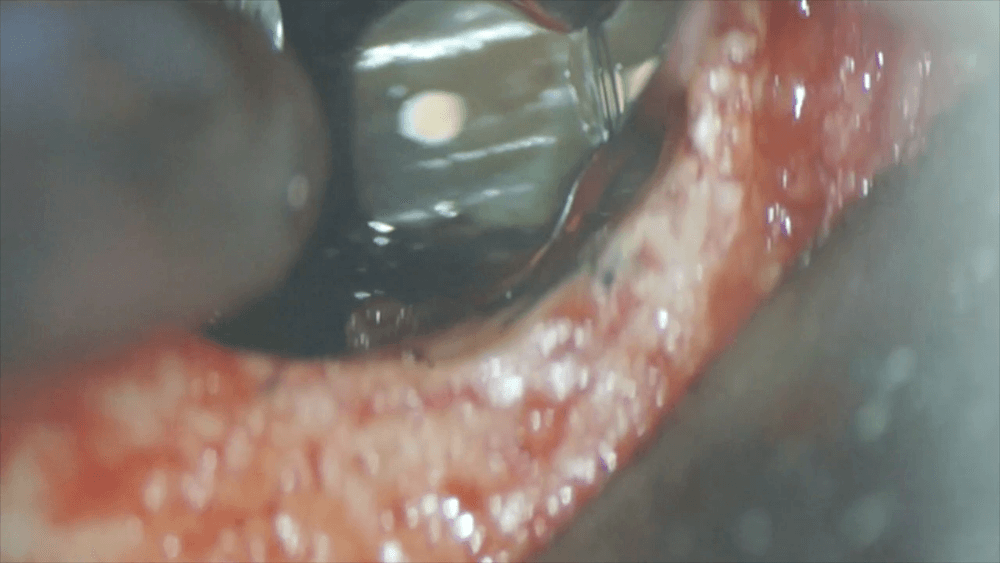

歯茎の裏側を見ると、こんなに骨が溶けています。根の先の炎症は恐ろしいですね。根の表面を確認すると、黒い石のようなものがへばりついています。これは、歯石です。これが、今回の症状の原因です。

マイクロスコープを用いて、処置を行います。まずは、根の先をカットします。と、同時に歯石も取り除きます。